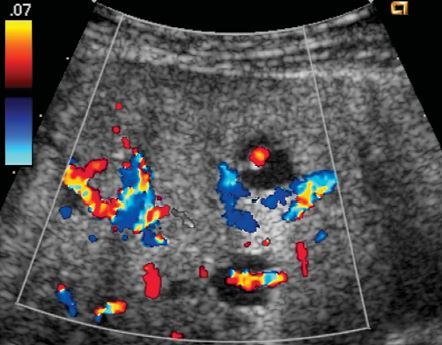

1. capsular artery

2. centripetal artery

3. recurrent artery

4. transmediastinal artery

5. transmediastinal vein